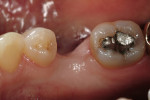

In vitro studies have demonstrated that the use of unidirectional glass-fiber reinforcement in the connector areas of FPDs contributes to significant composite reinforcement.29,36-38,66-68 Similar findings have been reported with a leno-weave UHMWPE and triaxial weave UHMWPE fiber.20,33,36 Fiber-reinforcing materials used by a dental laboratory are either resin pre-impregnated glass fibers, pre-polymerized composite resin surrounding glass fibers, biaxial braid UHMWPE, leno-weave UHMWPE, or a triaxial weave UHMWPE (Table 3). Typically, the preparation designs for the abutment teeth are inlay or onlay preparations (Figure 6A, Figure 6B, Figure 6C, Figure 6D). They are highly successful and can provide the patient with clinical service for more than 5 to 10 years.69 These restorations must be cemented using an adhesive resin technique with resin cements. Both etch-and-rinse adhesives with a self-cure or dual-cure composite resin cement or with a self-adhesive resin cement are indicated for cementing these restorations (Figure 7).36-38,70 Also, fiber-reinforcing materials are being used by dental laboratories in the fabrication of provisional restorations to reinforce and strengthen acrylic and composite-resin provisional materials.15,40,71